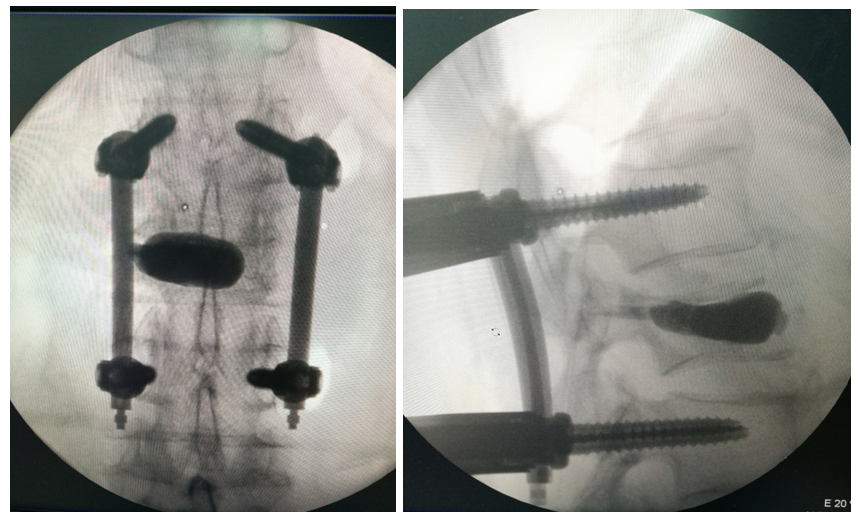

术后影像学

术中透视